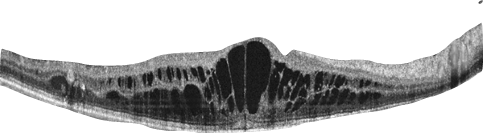

Рисунок 2. ОКТ-изображение диабетического отека макулы

При всех вышеописанных формах ретинопатии может отмечаться повреждение желтого пятна, проявляющееся его отеком или ухудшением кровоснабжения. Желтое пятно, или макула – это центральная часть сетчатки, которая отвечает за четкое зрение, необходимое для чтения и других точных действий. Повреждение желтого пятна приводит к снижению остроты зрения, в т. ч. к ухудшению зрения при чтении и появлению искажений.

При некоторых диабетических поражениях глаз иногда требуется инъекционное введение лекарства в глаз (в стекловидное тело). Уколы необходимы, если имеется диабетическая отечность желтого пятна и/или при наличии новых кровеносных сосудов и сопутствующих осложнений.

Точно изучить глазное дно можно только через расширенный зрачок. Для его расширения применяют специальные глазные капли, которые на время делают зрение нечетким. При необходимости делаются также цветные фотографии глазного дна, чтобы можно было отслеживать происходящие изменения. Для диагностики повреждения желтого пятна проводится оптическая когерентная томография (ОКТ) этого участка. Проверку глаз проводит прошедшая специальное обучение медицинская сестра, оптометрист или офтальмолог.